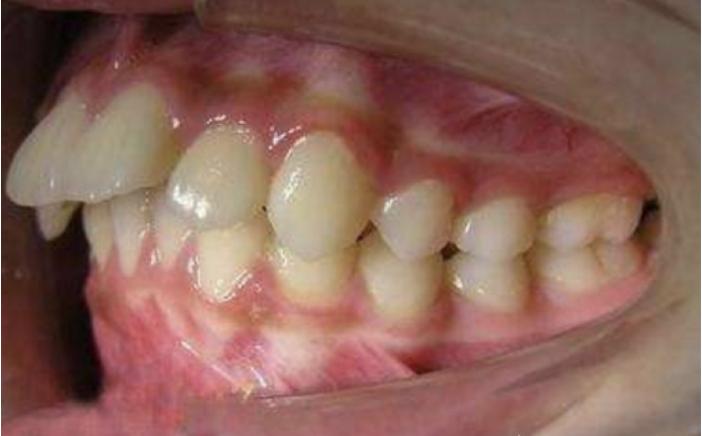

牙齿唇倾度越大,牙齿内收的范围也就越大;牙齿直立,内收范围较小。轻度骨性龅牙、唇倾度大的患者,通过单纯正畸治疗是可以有很大范围内收的,但是因为骨皮质没有切开,同时牙齿内收,正畸后牙轴会变得比较直立。如果正畸前“牙齿内收但是牙槽骨 前凸 ”“牙不凸但是嘴很凸”这种情况就不适合单纯正畸,强行移动牙冠会使牙轴更加直立,甚至“牙根冲出牙槽骨”。这样的患者单纯正畸内收的范围非常有限,需要通过骨皮质切开辅助治疗。

自测方法:观察自己的牙齿是否“飞出去”造成龅牙?还是牙齿直立,牙槽骨凸出造成的龅牙?

牙齿“飞出去”造成龅牙

牙齿直立,牙槽骨凸出造成的龅牙